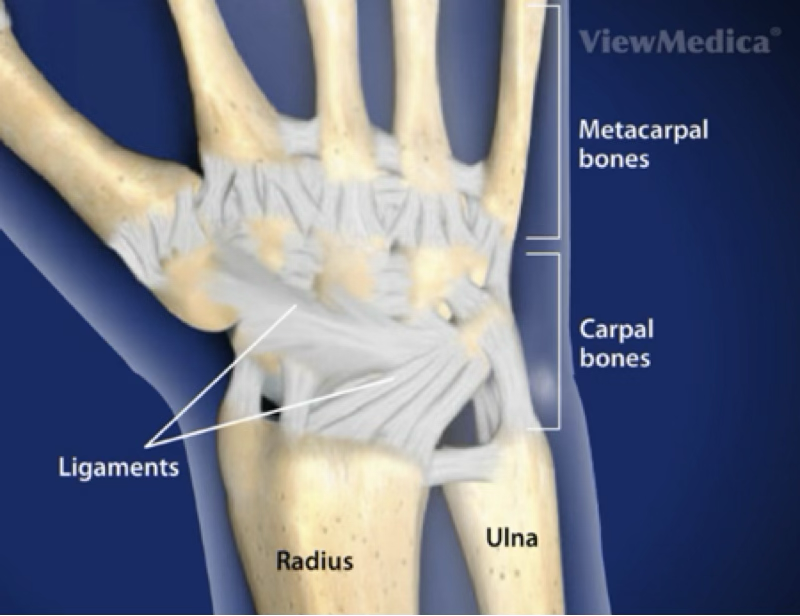

bones in the hand

8 carpals, 5 metacarpals, 2 sesamoids, 14 phalanges

MCP, MP, DIP, PIP joints